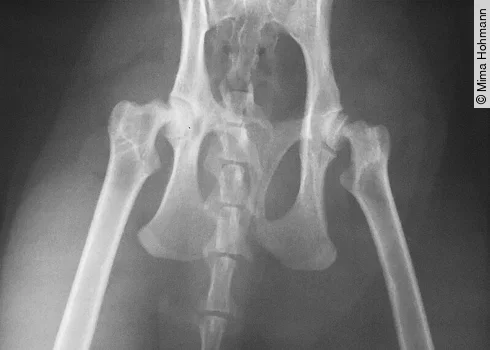

Schmerzen in der Wirbelsäule, meist im Übergang Lendenwirbelsäule/Kreuzbein ([Abb. 2])

Schmerzen im Hüftgelenk oder den Hüftgelenken ([Abb. 4])

Was kann man tun? Man sollte eine ausführliche klinische Untersuchung durchführen mit Harnuntersuchung und eventuell auch einem Röntgenbild, wenn man bei der Untersuchung Schmerzen und/oder muskuläre Verspannungen an den Gelenken ([Abb. 3]), der Wirbelsäule oder im Abdomen feststellt. Dabei sollten die Gelenke auch passiv durchbewegt werden.

Im Alter leiden über 50 % der Katzen unter Osteoarthrose (DVG-Tagung Berlin, November 2016). Hier einige Beispiele für die Osteoarthrose bei der Katze: